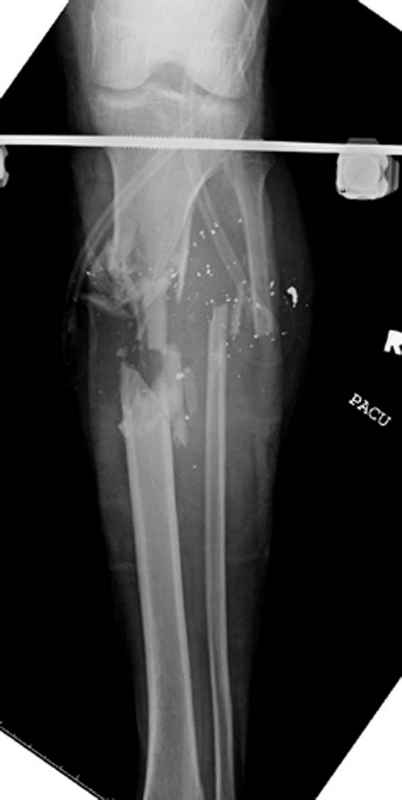

Уважаемые коллеги, Современная тактика лечения огнестрельных переломов вызывает споры. Опыты многих стран доказывает, что открытые переломы можно успешно лечить с применением внутренних металлических конструкций, включая гвозди. В западных странах более 25 лет эту методику применяют для лечения огнестрельных переломов. После применения адекватных методов по предупреждению осложнений, например, после промывания ран, огнестрельные переломы можно стабилизировать без боязни инфицирования. Здесь представлен больной 27 лет с ранениями, включая огнестрельный перелом большеберцовой кости. Стандартный аьгоритм: 11.08.09 доставлен в операционную, Irrigation&Debridment c фиксацией Наружным Фиксатором и вакуумирование VAC; службой травмы пройзведена ангиография с негативным результатом. (снимки 1-10) 14.08.09 повторная Irrigation&Debridment (чувстительственность из раны негативная) со сменой фиксации на медуллярный гвоздь и вакуумирование VAC 18.08 и 21.08.09 Irrigation&Debridment с сменой е VAC, после высеялся MRSA in thio т.е. на специальных срезах небольшое количество (11-13) 25.08.09 повторная Irrigation&Debridment. Пластик хирург не стал рисковать с Soleus flap из-за отечности, и применен Gastric flap, кожная пластика на медиальную и латеральную рану; аллографт из костных стружек с BMP. Поверхность вакуумирована VAC системой на 4 дня (14-16) Финальные снимки сделаем на днях. Djoldas Kuldjanov, MDDepartment of Orthopedic SurgerySt. Louis University Medical Center